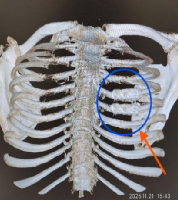

11月,患者胡先生(化名)因车祸伤导致多处肋骨骨折进入我院心胸外科治疗。

因其右侧第4、第5后肋骨折断端错位较重、错位骨折部分重叠、患者疼痛较重(见图一、图二);考虑其术后生活需求,错位的肋骨需要较好的复位,在和患者充分沟通后,制定了肋骨骨折内固定手术治疗。

图一 图二